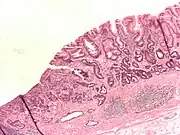

- Gastric adenocarcinoma is a malignant epithelial tumour, originating from glandular epithelium of the gastric mucosa. Stomach cancers are about 90% adenocarcinomas.[55] Histologically, there are two major types of gastric adenocarcinoma (Lauren classification): intestinal type or diffuse type. Adenocarcinomas tend to aggressively invade the gastric wall, infiltrating the muscularis mucosae, the submucosa and then the muscularis propria. Intestinal type adenocarcinoma tumour cells describe irregular tubular structures, harbouring pluristratification, multiple lumens, reduced stroma ("back to back" aspect). Often, it associates intestinal metaplasia in neighbouring mucosa. Depending on glandular architecture, cellular pleomorphism and mucosecretion, adenocarcinoma may present 3 degrees of differentiation: well, moderate and poorly differentiated. Diffuse type adenocarcinoma (mucinous, colloid, linitis plastica or leather-bottle stomach) tumour cells are discohesive and secrete mucus, which is delivered in the interstitium, producing large pools of mucus/colloid (optically "empty" spaces). It is poorly differentiated. If the mucus remains inside the tumour cell, it pushes the nucleus to the periphery: "signet-ring cell".

Poor to moderately differentiated adenocarcinoma of the stomach. H&E stain. -

Adenocarcinoma of the stomach and intestinal metaplasia. H&E stain.